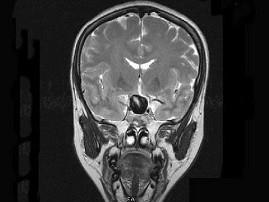

女,43岁,反复头痛10个月,CT检查如图,最可能诊断为 ( )A、脑膜瘤B、胶质瘤C、垂体瘤D、颈内动脉瘤E、颅咽管瘤

问题 女,43岁,反复头痛10个月,CT检查如图,最可能诊断为 ( )

选项 A、脑膜瘤 B、胶质瘤 C、垂体瘤 D、颈内动脉瘤 E、颅咽管瘤

答案 D